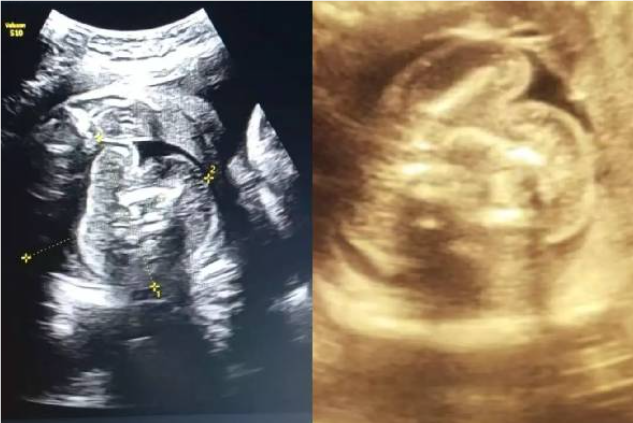

கர்ப்பிணியின் வயிற்றில் உள்ள குழந்தைக்குள் வளரும் கரு – மிரண்ட மருத்துவர்கள்!

பெண்ணின் வயிற்றில் உள்ள குழந்தைக்குள் கரு வளரும் சம்பவம் ஆச்சர்யத்தை ஏற்படுத்தியுள்ளது.

சிசுவுக்குள் கரு

மகாராஷ்டிராவில் புல்தானா மாவட்டத்தின் அரசு பெண்கள் மருத்துவமனை செயல்பட்டு வருகிறது. இங்கு 9 மாத கர்ப்பிணி சிகிச்சை பெற்று வந்துள்ளார்.

அவருக்கு சோனோகிராபி செய்தபோது அவரின் கருவில் முழு வளர்ச்சியடையாத கரு வளர்வது கண்டறியப்பட்டுள்ளது. இதுகுறித்து அந்த மருத்துவமனையின் மகப்பேறு மருத்துவர் பிரசாத் அகர்வால் கூறுகையில்,

ஆரம்பத்தில் நான் ஆச்சரியமடைந்தேன், பின்னர் கவனமாக ஸ்கேனை மறுபரிசீலனை செய்தேன். இது முந்தைய சோனோகிராஃபியில் தவறவிடப்பட்டது. ஏனெனில் இது மிகவும் அரிதான நிலை. இதுபோன்ற ஒரு நிலை இருக்கும் என்று யாரும் கற்பனை கூட செய்ய முடியாது.

எனவே, நான் இரண்டு மருத்துவர்களிடம் விரிவான ஆலோசனைக்கு பின் அதை உறுதி செய்தேன் எனத் தெரிவித்துள்ளார். இந்நிலையில், அந்த பெண் பிரசவத்திற்காக மருத்துவமனையில் அனுமதிக்கப்பட்டுள்ளார்.

இதுவரை உலகில் வெறும் 200 பேருக்கு மட்டுமே இதுபோல நிகழ்ந்துள்ளது. 5 லட்சத்தில் ஒருவருக்கு மட்டுமே நடக்கக்கூடிய நிகழ்வு. இந்த நிலைக்கான சரியான காரணம் எதுவும் கூறப்படவில்லை. ஆனால், இது ஒரே மாதிரியான இரட்டையர்களின் வளர்ச்சியின் போது நிகழும் ஒழுங்கின்மையின் விளைவு என கருதப்படுகிறது.